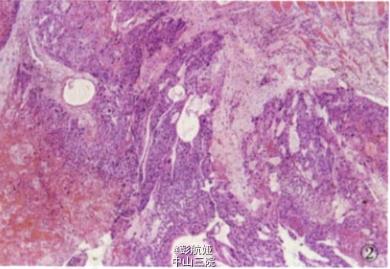

眼观:手臂肿块切除标本1个,大小4 cm×4cm×3 cm,其内见暗红色肿物,切面肿物界清,中央见大片暗红色出血、坏死区,周边少许灰红色区,质软。镜检:肿瘤组织内见大片出血、坏死,间质稀少;瘤细胞呈多边形,境界清楚,细胞质淡染或透亮,核圆形位于中央,核仁明显,此类细 胞成片排列,其间夹杂一团团的合体型细胞,胞质丰富、深染、嗜酸,细胞核多个、增大深染或皱缩(图2)。提示异型肿瘤细胞,巢团状浸润性生长,间质大片出血坏死,初步诊断为生殖源性恶性肿瘤,复查血HCG大于200 000 mlU/ml,尿HCG强(+),免疫组化结果显示:CK(+),HCG(+),HPL (+),AFP(一)。经病理提示绒癌可能后,再次体检发现患者一侧睾丸肿大,有男性乳腺发育特征。

病理诊断:男性绒毛膜癌,并发肝、肺、脑、手臂转移。本例并发肝、肺、脑、手臂多处转移灶,已经出现胸、腹部症状,经化疗无效,最后出现呼吸衰竭自动出院。